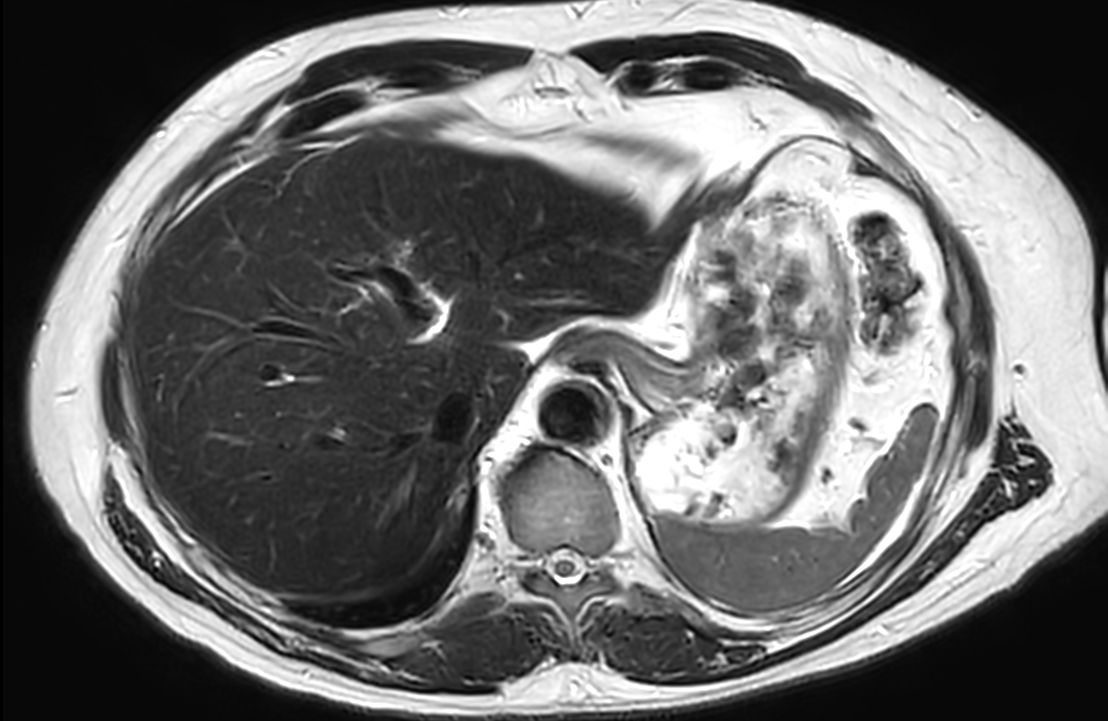

Liver imaging case, leveraging Philips SmartSpeed, our breakthrough new MRI application that delivers image and speed without compromise. Building on our proven technology and leveraging AI* to take fast MRI technology to the next level. Imaging speed is increased while providing greater resolution to deliver outstanding image quality. It covers motion imaging, free-breathing imaging and diffusion-weighted imaging to address the needs of a broad range of patients in various conditions.

Axial T2w TSE mDIXON (out-phase)SmartSpeed Diffusion